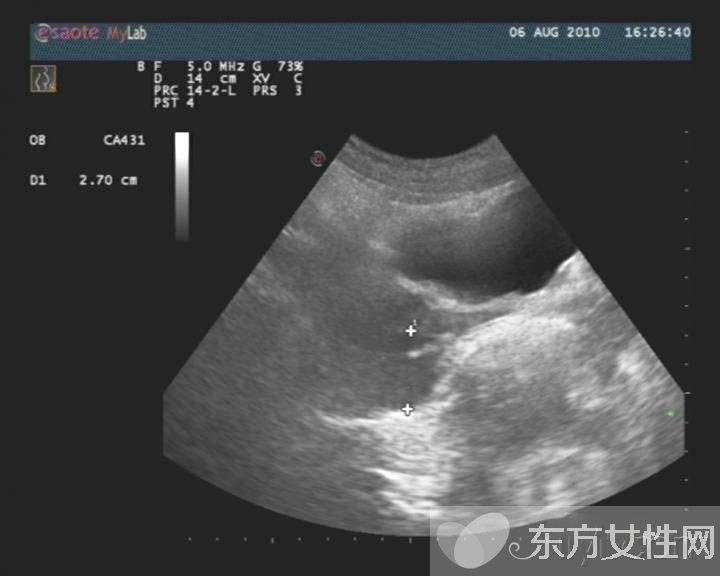

盆腔炎是指女性盆腔生殖器官、子宫周围的结缔组织及盆腔腹膜的炎症,主要包括子宫内膜炎、输卵管炎、输卵管卵巢脓肿、盆腔腹膜炎。

慢性盆腔炎常为急性盆腔炎未能彻底治疗,或患者体质较差,病程迁延所致。它可使机体发生慢性输卵管炎与输卵管积水、输卵管卵巢炎及输卵管卵巢囊肿、慢性盆腔结缔组织炎。

(5)冲任虚寒型:小腹冷痛,喜暖喜按,带下量多色白质稀,畏寒肢冷,舌质淡,苔薄白,脉沉细。常用中成药内服丸剂具有清热解毒、活血化瘀等作用,可综合用药。女性生殖系统,任何一方面的疾病都可能引发盆腔炎,这个问题可大可小,容易导致不孕不育,一定要治疗。盆腔积液就是盆腔存在炎性渗出物,可发生在子宫内膜发炎后,内膜组织肿胀的细胞中渗出的略黏稠的液体,被周围组织包裹所渐渐形成的囊性包块。